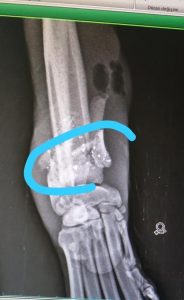

Bolu’dan üç bacağı kırık olarak gelen köpeğimizin, çekilen röntgenler sonrasında bacaklarından kurşunlandığı ortaya çıkmıştır. Maalesef kurşunlar dolayısıyla kemikleri paramparça haldedir. Tedavi süreci başlamıştır.